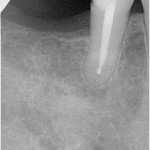

Röntgenbefund: unvollständige WF, ausgedehnte chronische apikale Parodontitis bei alter WSR

Chronische apikale Parodontitis nach WSR (ca. 10 Jahren)

- Röntgenkontrolle: PAC geht zurück.

- Röntgenkontrolle: PAC geht weiter zurück, Parodontalspalt schwach zu erkennen.

- Röntgenkontrolle: PAC ausgeheilt.

- Röntgenkontrolle 5 Jahre nach Wurzelfüllung: apikal o. B.

Die Röntgenkontrollen am 17.06.2002, 21.10.2002 und 21.06.2004 zeigen eine vollständige Ausheilung der chronischen apikalen Parodontitis. Die Röntgenkontrolle nach 5 Jahren zeigt einen stabilen Zustand, so dass die damalige Entscheidung wohl die richtige Wahl war.